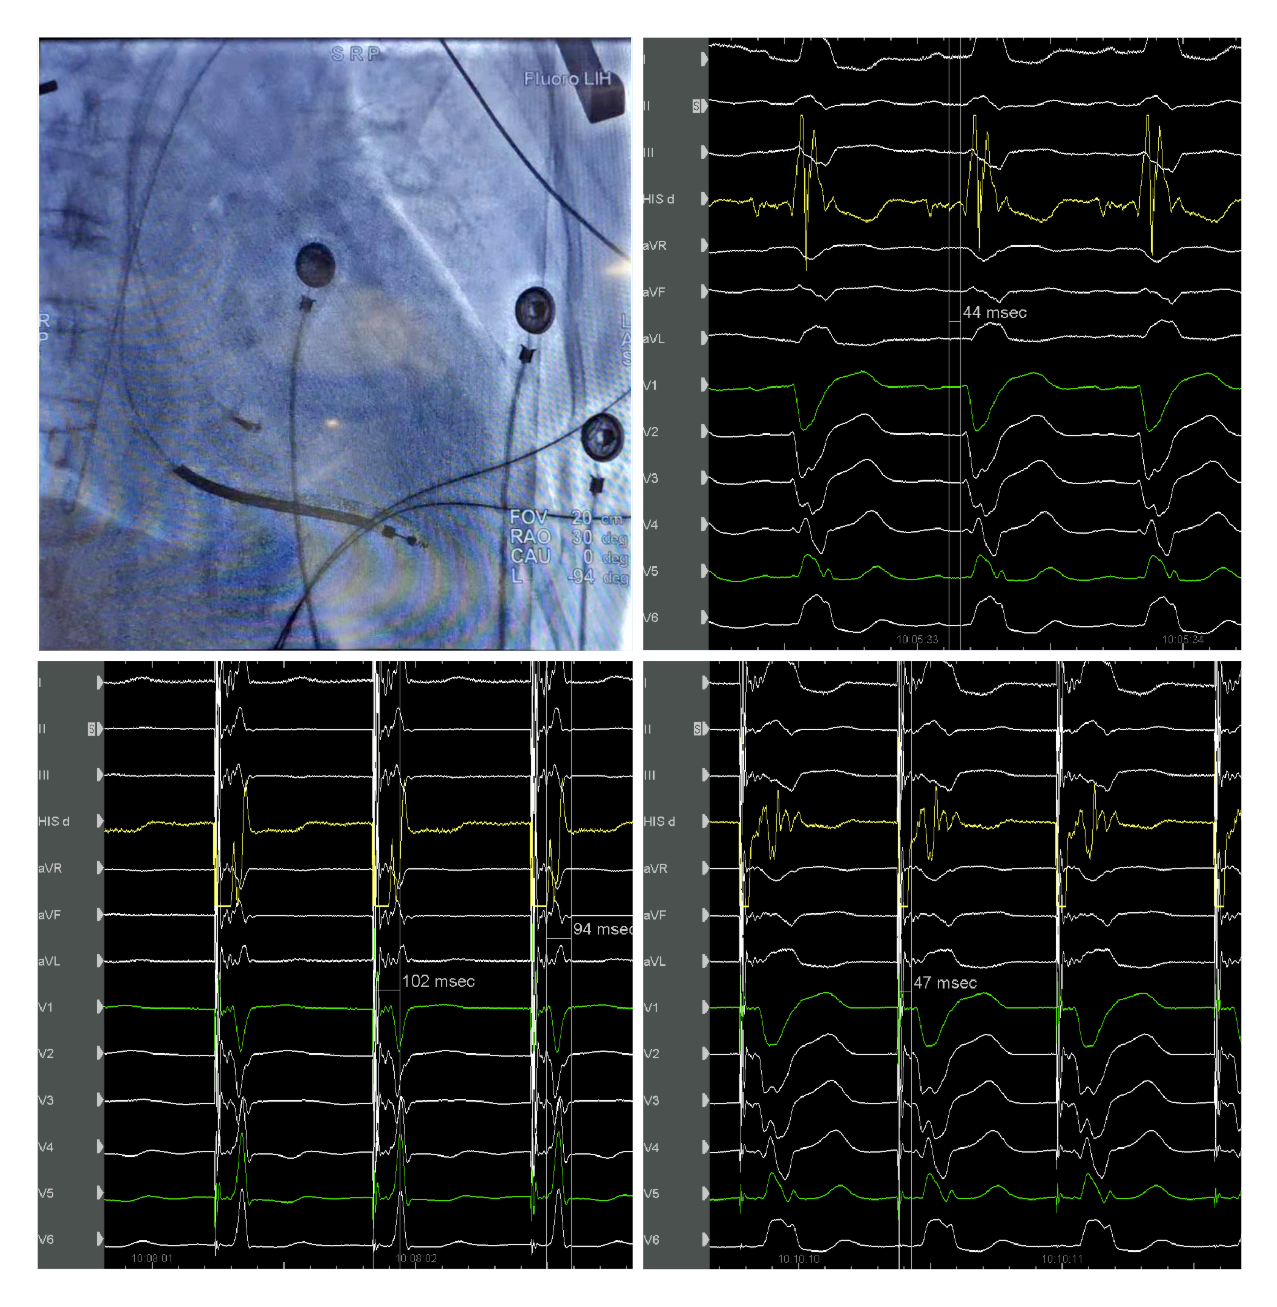

我院起搏团队演示了一例左束支起搏纠正完全性左束支阻滞用于治疗经典CRT适应症的病例。该患者为女性, 69岁,诊断:扩张型心肌病,完全性左束支传导阻滞,心功能III级,心电图显示经典完全性左束支阻滞图形,QRS193ms,心超LVD 73mm,EF 30%,符合CRTD适应症。术中顺利穿刺左侧腋静脉,在C315鞘管导引下3830电极标记到HIS电位,高电压起搏可纠正左束支阻滞,但纠正阈值较高8V/1.5ms。

(上图左上为希氏束的影像位置;右上为希氏束电位图;右下为低电压选择性希氏束起搏波型与自身一致;左下为高电压8V/1.5ms希氏束起搏纠正完左)

随后3830导线往心尖方向前移1cm拧入,同时监测起搏图形及单极阻抗,到位后起搏心电图显示不完全性右束支阻滞图形,左束支阻滞消失,测量V5导联左室达峰时间84ms,单双极高低电压起搏一致,提示夺获了左束支,夺获阈值0.7V/0.5ms。

(上图中左上为单极高电压起搏,右上为单极低电压起搏,左下为双极高电压起搏,右下为双极低电压起搏)

之后顺利植入心房导线及除颤导线,连接CRTD,调整AV间期融合右束支下传后得到完全正常化的QRS图形,起搏QRS时限97ms。